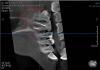

Екатерина У Опубликовано 3 марта, 2011 Поделиться Опубликовано 3 марта, 2011 (изменено) Когда начали лечить 26 зуб на обычном рентгеновском снимке никаких образований на корне (корый самый длинный) обнаружено не было. Потом я сделала КТ. Там на этом корне что-то похожее на гранулёму, но это заметно при определённом угле поворота проекции. Посмотрите, интересует мнение со стороны, т.к. мой врач говорит, что на гранулёму не похоже. Зуб пока продолжаем проходить. Изменено 3 марта, 2011 пользователем Екатерина У Ссылка на комментарий

Екатерина У Опубликовано 3 марта, 2011 Автор Поделиться Опубликовано 3 марта, 2011 (изменено) Екатерина!На срезе КТ отабражен нижний зубной ряд, а лечили зуб верхний слева. Т.е. это разные анатомические области. В нижней шестерке очаг десрукции костной ткани на мезиальном корне. Нет, всё правильно, такой разворотсейчас попробую с головой сделатьтам сверху ещё видно начало гайморовой пазухирасположение головы снизу справа на картинке (откуда смотрим разворот) Изменено 3 марта, 2011 пользователем Екатерина У Ссылка на комментарий

Екатерина У Опубликовано 11 марта, 2011 Автор Поделиться Опубликовано 11 марта, 2011 Вот, смотрите. Вроди бы что то есть, на на коце корня вроди бы ничего нет. И дальше тоже нет, посмотрела. Думаю это не гранулёма..... Ссылка на комментарий